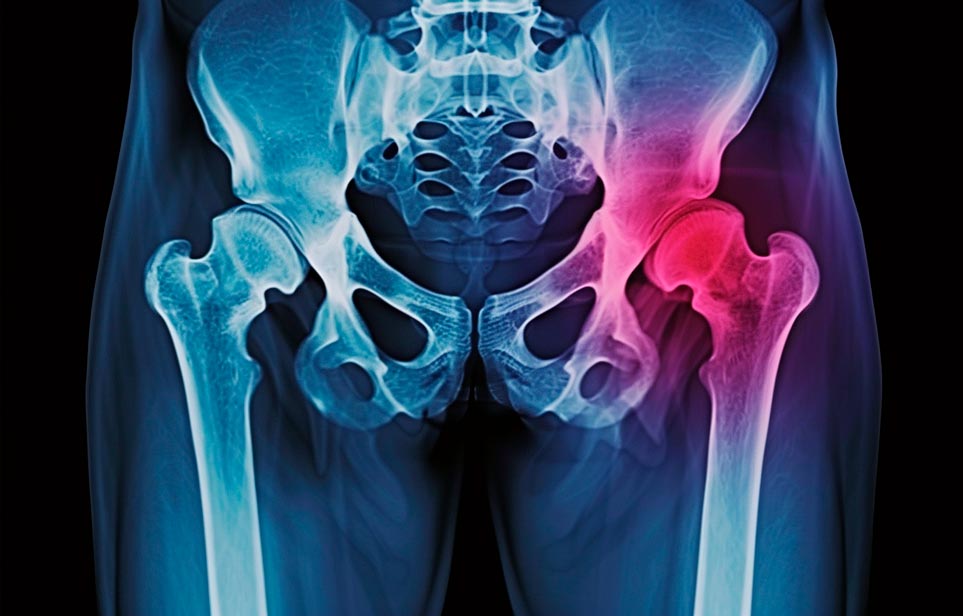

Реабилитация пожилых после перелома шейки бедра в Армянске

Эффективная и профессиональная реабилитация после перелома шейки бедра в Армянске осуществляется по демократичным ценам лучшими специалистами современной медицинской клиники «Заботливые люди» с применением персонального подхода к каждому пожилому человеку с такой тяжёлой травмой бедренной кости ноги. В процессе осуществления такой специализированной услуги все наши пациенты имеют возможность получения качественного и достойного обслуживания, эффективного восстановления. Лучший дом престарелых позаботиться о Вашем близком человеке.

Такая травма в большей части случаев возникает у граждан преклонного возраста. При её появлении на протяжении длительного времени сохраняются болевые и неприятные ощущения в области паха, при которых серьёзно ухудшается качество жизни, возникает множество последствий для его жизни и здоровья.